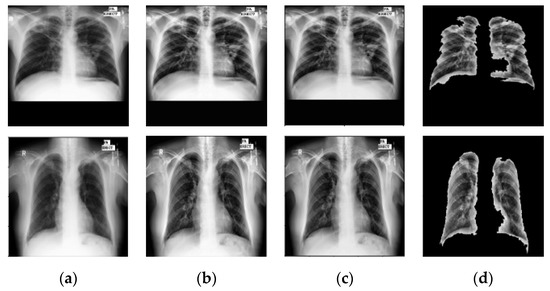

6.2. Prior TB Segmentation